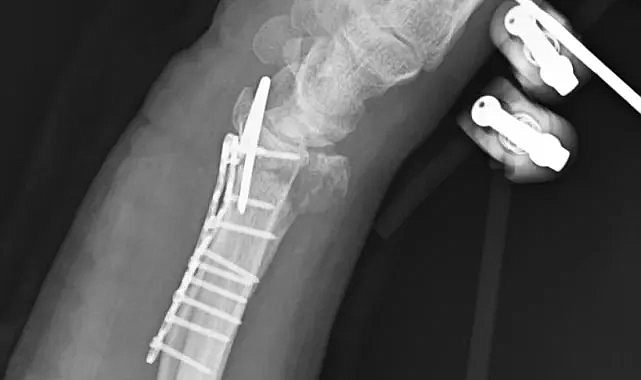

Köpeklerin bacaklarını ısırmaya çalıştığı sırada dengesini kaybeden Arslantaş, kamyonetin kasasından düşerek yere savruldu. Yaşanan olay sonrası yaralanan Arslantaş, 112 Acil Servis’i arayarak yardım istedi.Ambulansla hastaneye kaldırılan Arslantaş’ın sağ kolunda bilek kısmında parçalı kırık oluştuğu belirlendi.Hastanede yaklaşık 3–3,5 saat süren bir ameliyat geçiren Yasin Arslantaş, tedavisinin ardından taburcu edildi. Doktorlar, kırığın parçalı olması nedeniyle tam iyileşmenin zor olabileceğini, his ve hareket kaybı yaşanabileceğini belirtti.Arslantaş’ın en az 2 ay fizik tedavi görmesi gerektiği öğrenildi.“Köpekleri Gördükçe Yolumu Değiştiriyorum”